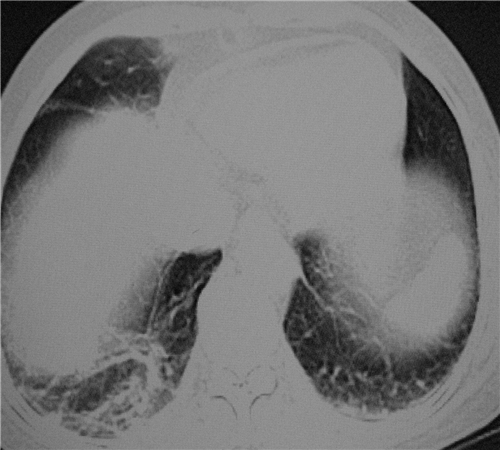

标题: CT26849:女67岁反复胸痛两天余,临床考虑夹层。

双下肺感染,右侧显著。有无夹层,增强扫描后再诊断。

1. 感染性病变,2.未见夹层,3.食道未见异常。

1.考虑双肺感染,右侧为重;2.建议ct增强或mri排除主动脉夹层

双下肺感染,右侧显著。有无夹层,增强扫描后再诊断。食道未见异常。